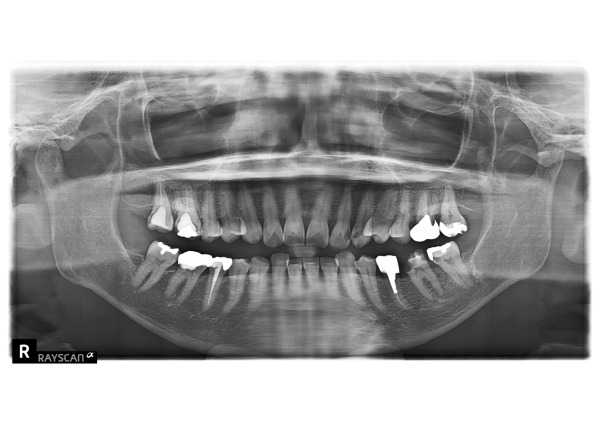

エックス線を撮影すると、右上奥歯2本、左下奥歯2本、左上前歯2本に虫歯が認められました。エックス線写真で診断するより実際は虫歯が深いことがあります。左下6番、左下7番、左上2番の計3本が神経に到達するほどの大きい虫歯でした。